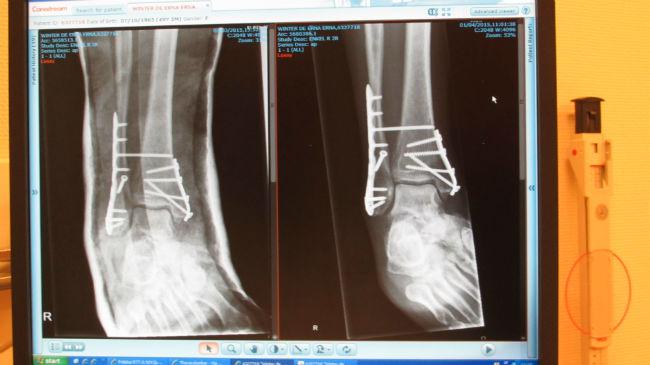

Dit was de stand van zaken vorige week...

Links is met gips vlak na de operatie, rechts is duidelijk minder gezwollen enkel zonder gips.